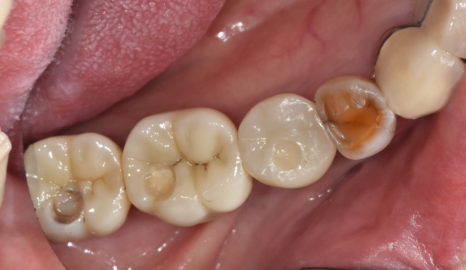

식사를 할 수 있는

어금니가 여러군데 빠진채로 내원해주신 환자분입니다.

치아 개수가 빠진게 많다보니

그러려니~ 하고

사셨다고 하네요ㅠㅠ

23.06.13

오른쪽 왼쪽 각각 1개 치아만

물리고 있는 상황이라

더이상은 버티시기 힘드셨대요

자연 치아 중에서도

많이 닳고 좋지는 않았지만

워낙 상실된 치아가 많아서